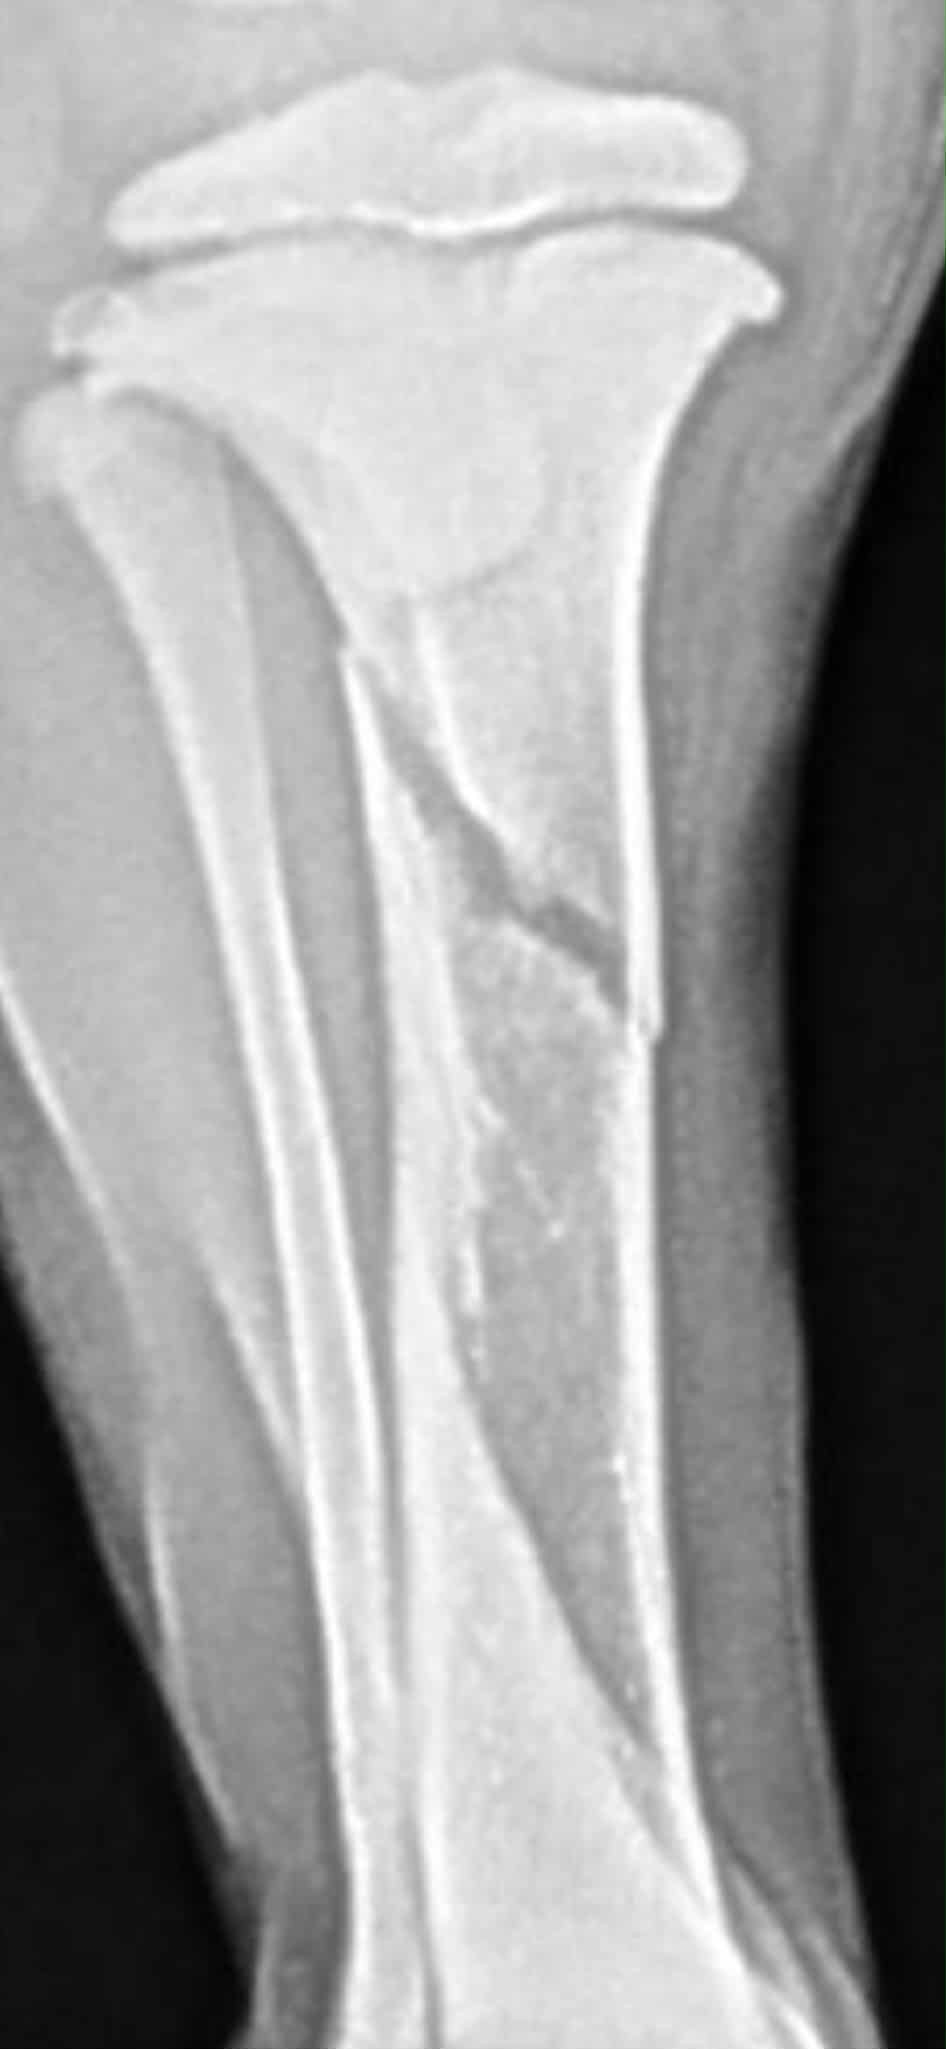

I wanted to share a wonderful update! Charlie was seen at her follow up to be assessed for surgery, and will not require pins and plates <3 She still has a long way to go, with her tibia broken, she is now casted, and will require new casting every 10 days (as she is a growing pup) and repeat images at 1 month out and then 2 months out to make sure she is healing properly... but this is such great news. Help is still needed for her family, if possible, and is so much appreciated!

Poor baby Charlie has sustained a break in her little leg requiring a plate and screws. Charlie is just 11 weeks old and has just found her forever home. However, it is extremely difficult for her family to cover the needed surgery. Any help you could lend is much appreciated!